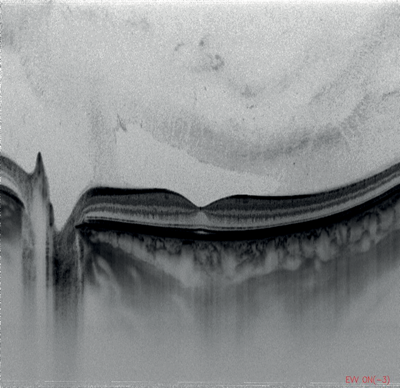

Figures 1-4: Swept-source OCT (DRI OCT-1 Triton, Topcon) images of healthy eyes that clearly delineate features in the vitreous, including area of Martegiani, bursa premacularis and posterior hyaloid, right through to the sclera, in the same single scan.

Figure 5: Colour fundus photograph of healthy eye taken

using swept-source OCT (DRI OCT-1 Triton, Topcon).